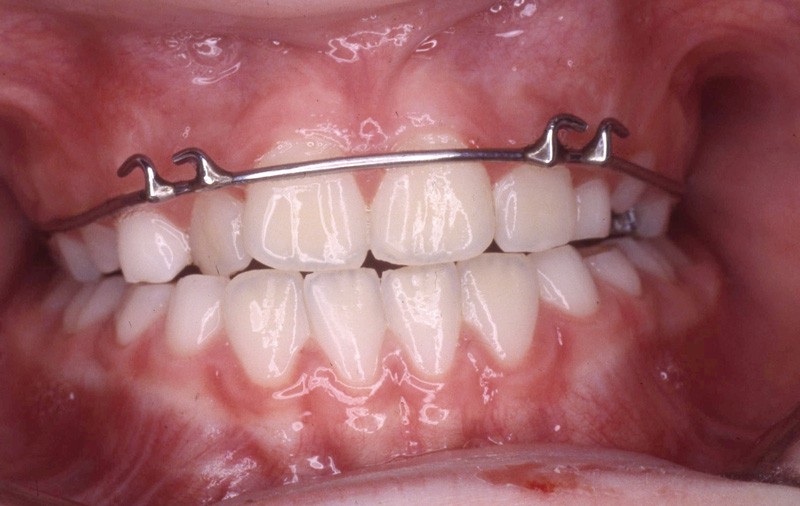

Pendant cette première étape de traitement, les tractions postéro-antérieures sont portées la nuit, soit 8 à 9 h /24 h, sur masque de Delaire pendant 13 mois, avec des tractions d’environ 800 g (fig. 7 à 9).